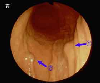

Blue Rubber Bleb Nevus syndrome with multiple angiomas of the G-1 tract, tongue, lip and hand.

Endoscopy

Non-epithelial tumors/Hemangioma, Lymphangioma